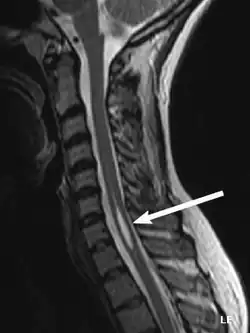

| An idiopathic syrinx | |

Physicians now use magnetic resonance imaging (MRI) to diagnose syringomyelia. The MRI radiographer takes images of body anatomy, such as the brain and spinal cord, in vivid detail. This test will show the syrinx in the spine or any other conditions, such as the presence of a tumor. MRI is safe, painless, and informative and has greatly improved the diagnosis of syringomyelia.[18]